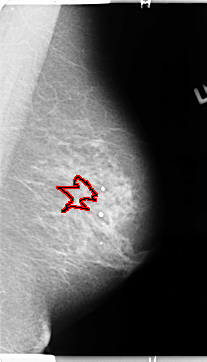

FILE: B_3123_1.LEFT_MLO.OVERLAY

TOTAL_ABNORMALITIES 1

ABNORMALITY 1

LESION_TYPE MASS SHAPE ARCHITECTURAL_DISTORTION MARGINS ILL_DEFINED

ASSESSMENT 3

SUBTLETY 2

PATHOLOGY BENIGN

TOTAL_OUTLINES 1

BOUNDARY